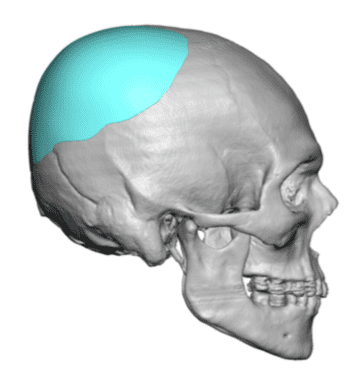

Desire for an improved head shape so that it looks rounder and not so peaked or sloped.

Placement of custom skull implant for parasagittal augmentation to create a rounder head shape. An example of what appears to be a high sagittal crest that is really low parasagittal skull areas.

Desire for an improved head shape so that it looks rounder and not so peaked or sloped.

Placement of custom skull implant for parasagittal augmentation to create a rounder head shape. An example of what appears to be a high sagittal crest that is really low parasagittal skull areas.